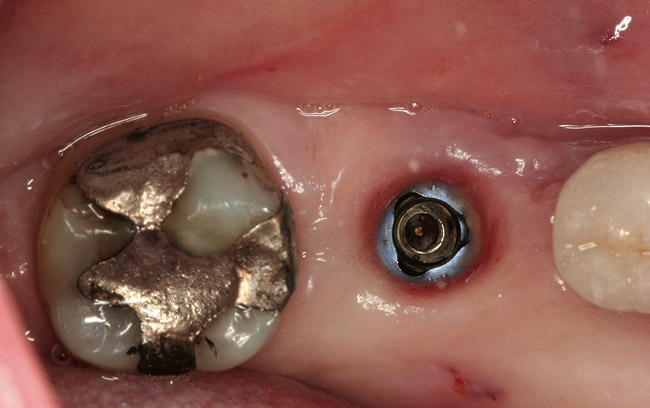

Figure 2  Following crown and abutment removal, the implant platform was exposed.

Figure 2